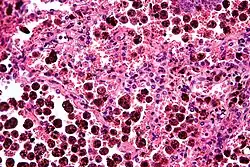

Comparison of pigmented pulmonary macrophages

| Disease | Macrophage name | Macrophage pigment appearance (HE stain) | Usual macrophage location | Associated medical history | Image | Image comment |

|---|---|---|---|---|---|---|

| Anthracosis | Black-brown granules | Interstitium (perivascular) |

|

Black arrow shows interstitial anthracotic pigment. Nearby macrophages (white arrow) can be presumed to contain anthracotic pigment. | ||

| Respiratory bronchiolitis | "Smoker’s macrophages" | Yellow to light brown and finely granular[4] | Airways (especially respiratory bronchioles) | Tobacco smoking |

Smoker's macrophage in center |

| Chronic pulmonary congestion | Siderophages | Brown-golden and refractile.[5] | Alveoli[6] |

Siderophage (black arrow), and interstitium with edema, hemosiderin deposition (black arrow) and collagenous thickening, indicating heart failure. |